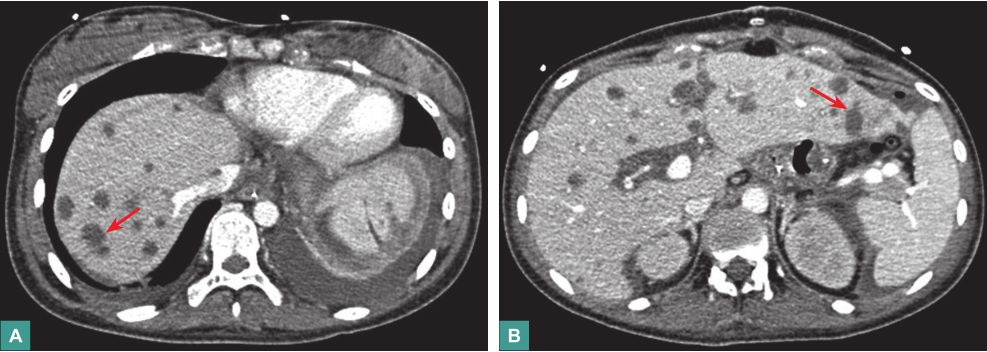

(3)腹部CT平扫

肝实质见多发低密度影,少量腹腔积液,脾大(图2)。

图2腹部CT表现

4.影像学检查

胸部X线片未见双肺感染性病变,心影正常。腹部CT可见肝内多发低密度灶,腹腔少量积液,脾大。

入院后,患者中上腹闷痛、腹胀无缓解,交替排黑便(50~550ml/d)和黄软便,血红蛋白最低降至65g/L。入院第11天,患者出现腹痛加剧,呕血400ml,排柏油样便量约600ml,意识淡漠,血压降至70/40mmHg,血红蛋白30g/L,予输血、升压处理后急行床旁胃镜检查,见胃黏膜大片状剥脱,黏膜下血肿形成,部分可见血管裸露,肌层显露,胃腔内大量血块形成,内镜下无法止血。立即全麻下急行剖腹探查术,术中见胃大部分区域缺血坏死,胃腔扩大明显,内可见大量血凝块,胃黏膜大片剥脱,累及浆膜层,肝表面见多发黄色脐乳样结节,遂行全胃切除+食管空肠Roux-y吻合+肝脏结节活检术。术后,患者循环系统逐渐稳定,血红蛋白升至100g/L。但术后第3天,患者再发中腹部闷痛,体温37.8℃,外周血WBC 17.8×109/L,CRP 123.00mg/L,腹腔引流液培养出热带念珠菌和屎肠球菌,遂继续予亚胺培南西司他丁钠、利奈唑胺联合米卡芬净抗感染治疗。复查腹部CT,示肝内低密度灶较前增多、增大(图5),肠系膜血管CTA未见异常。

图5腹部CT表现

腹部CT见肝内多发低密度灶较前增多,增强扫描病灶无强化